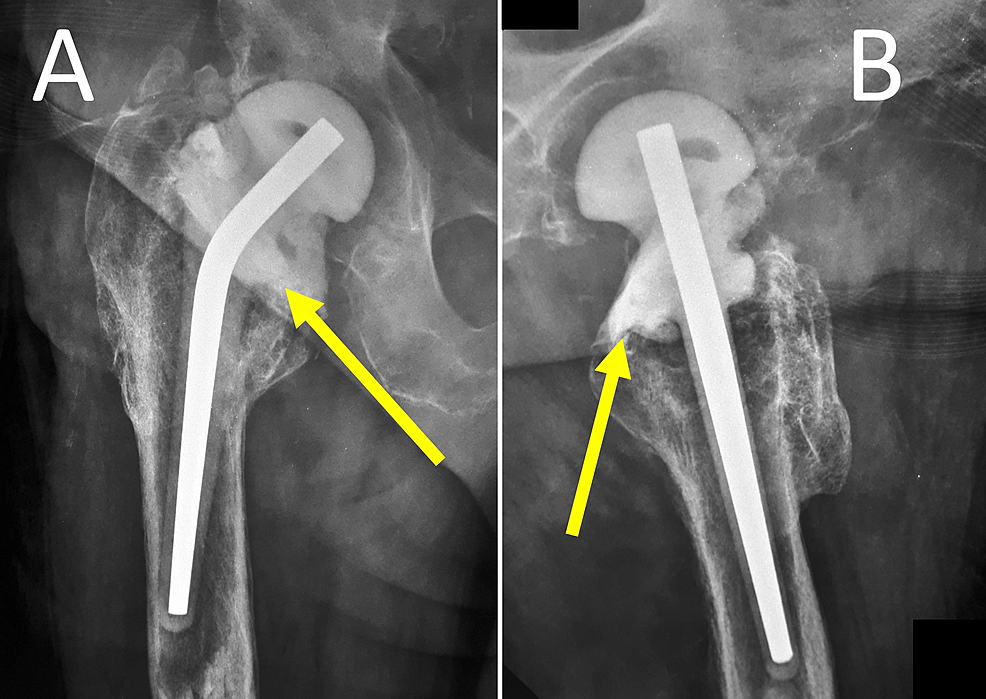

Anteroposterior radiographs of the hip spacer A) without cementation Hip Spacer Complications The rehabilitation program following hip spacer implantation emphasizes early, controlled functional range of motion to prevent hip. Temporary spacers used in the staged revision of a hip prosthetic joint infection (pji) have been associated with several mechanical. The use of “functional” spacers may allow patients to return to daily living while optimizing their health for revision surgery. The aim of. Hip Spacer Complications.